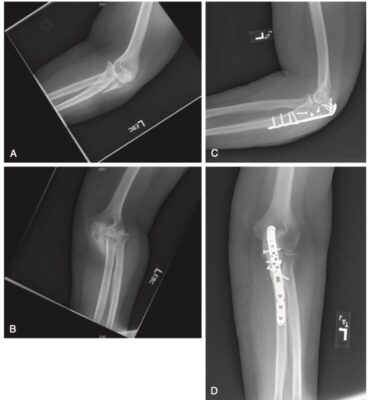

Gãy mỏm khuỷu

Khớp cánh tay trụ là khớp kiểu bản lề. Nó tạo thành hình bán nguyệt khi nó khớp với hố ròng rọc của đầu dưới xương cánh tay. Mỏm khuỷu tiếp khớp với hố mỏm khuỷu của xương cánh tay ở phía sau và mỏm vẹt khớp khớp với hố mỏm vẹt của xương cánh tay ở phía trước. Gãy mỏm khuỷu có thể xảy ra riêng lẻ hoặc cùng với các cấu trúc khác như chỏm quay, mỏm vẹt hoặc tổn thương các dây chằng bên của khuỷu tay. Các gãy xương đơn độc của xương trụ được phân loại theo phân loại Mayo (Morrey 1995).

Việc phân loại giúp đưa ra quyết định điều trị vì phân loại này dựa trên mức độ di lệch, số mảnh gãy, và độ vững của khuỷu tay. Gãy mỏm khuỷu di lệch tối thiểu và vững có thể được điều trị bằng các biện pháp không phẫu thuật. Thông thường khuỷu tay được đặt nẹp hoặc bó bột ở tư thế gập 90 độ trong 3 – 4 tuần với vận động chủ động nhẹ nhàng (Ring 2010).

Cố định mỏm khuỷu khi phẫu thuật bao gồm buộc dây, đinh (gãy đơn giản) hoặc nẹp vít (gãy phức tạp). Tập luyện có thể được bắt đầu một tuần sau phẫu thuật. Khuyến khích tập tầm vận động chủ động trợ giúp nhẹ nhàng. Tập chủ động chống lại kháng trở thường đợi đến khi có dấu hiệu liền xương (sau 6 – 8 tuần).